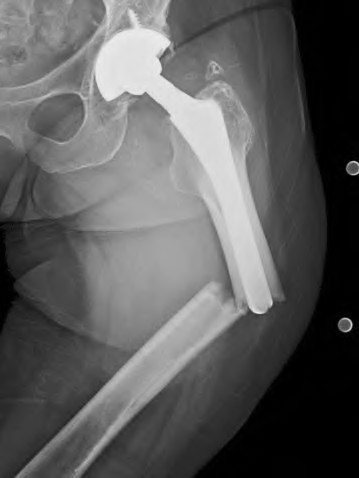

A 78-year-old female sustains a periprosthetic femur fracture 10 years after a cemented THA. Radiographs show a fracture around the tip of the stem with a loose femoral component and poor proximal bone stock, but adequate diaphyseal bone.

What is the most appropriate surgical treatment?

A 75-year-old female sustains a periprosthetic femur fracture around a cemented polished taper slip stem. Radiographs demonstrate a fracture around the tip of the stem. The stem is radiographically loose, but the proximal bone stock is excellent (Vancouver B2).

What is the gold standard surgical management?